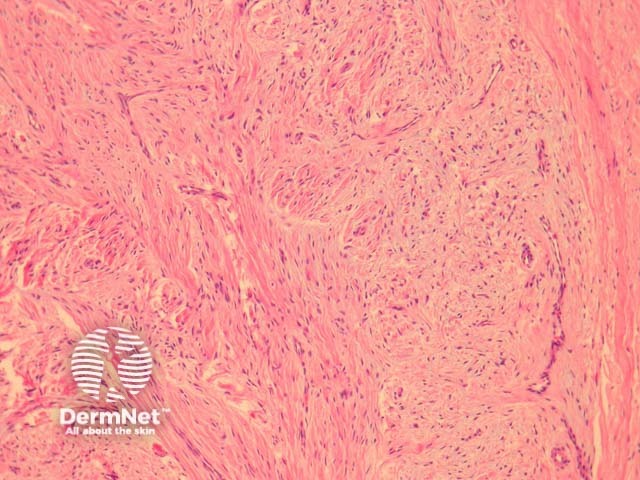

In superficial acral fibromyxoma, sections show a paucicellular fibromyxoid lesion arising in the dermis of acral skin (figure 1). Subcutaneous involvement is common. The cells are bland, spindled or stellate and set in a fibromyxoid stroma (figures 2 and 3).

Figure 2